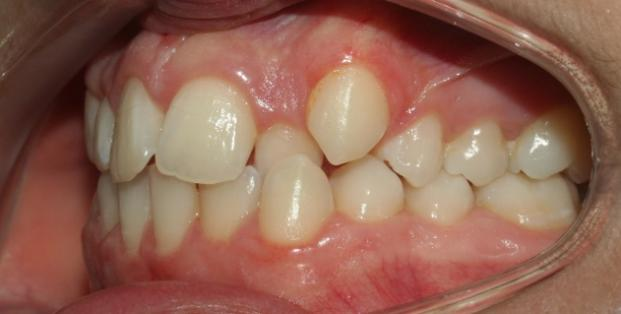

The patient in this case is a 15-year-old female who presented with mild third skeletal class with upper and lower tooth crowding at the beginning of the treatment. The whole process lasted for around 20 months employing traditional metal brackets.

Fig 1,2,3: the intraoral condition before orthodontics treatment & Fig 4,5,6: the intraoral condition after orthodontics treatment.